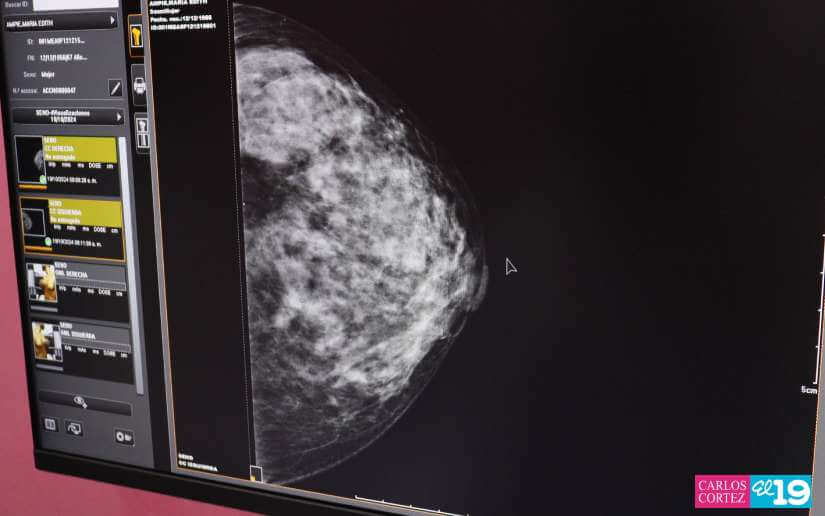

Durante la jornada se realizarán estudios de ultrasonido de útero, ultrasonido pélvico, ultrasonido de mamas, mamografías, ultrasonidos abdominales, ultrasonidos renales atención ginecológica, papanicolao, evaluación a las embarazadas, medicina natural, oftalmología, dermatología y valoraciones nutricionales.

"Estamos realizando esta mega feria de atención a las mujeres nicaragüenses en el marco de la campaña de protección de la salud de las mujeres contra el cáncer de mama. El objetivo es evaluar a todas las mujeres, hacerles una evaluación integral realizando ultrasonido de mamas, mamografías, en el caso de requerir biopsia se le van a realizar las tomas porque aquí tenemos patólogos para evaluar a cada mujer y esperamos en esta mega feria atender a unas 2500 mujeres y realizar unas 10,000 atenciones entre todos los servicios", explicó la doctora Carmen Marina Cruz Blandón.